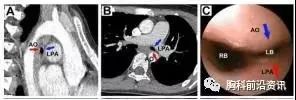

图1.患儿术前胸部CT及气管镜,左肺动脉干与胸主动脉压迫导致气管软化

了解患儿病情后,胸外科医生们先给患儿完成了薄层胸部增强CT和MRI检查,发现患儿存在左肺动脉干和胸主动脉的成角畸形,两条动脉长期挤压左主支气管导致管壁发生软化性狭窄。明确病因后,李小飞主任、黄立军副主任等高度重视患儿病情,考虑到患儿多次内科治疗效果不佳,于是先后讨论了多种外科手术方案,包括软化段气管切除术、气管成形术、主动脉悬吊术等,但都因手术复杂、风险大等原因放弃。结合胸外科前期在4D打印气管外支架方面的工作,综合分析患者病情决定为患儿施行4D打印气管外支架悬吊手术。